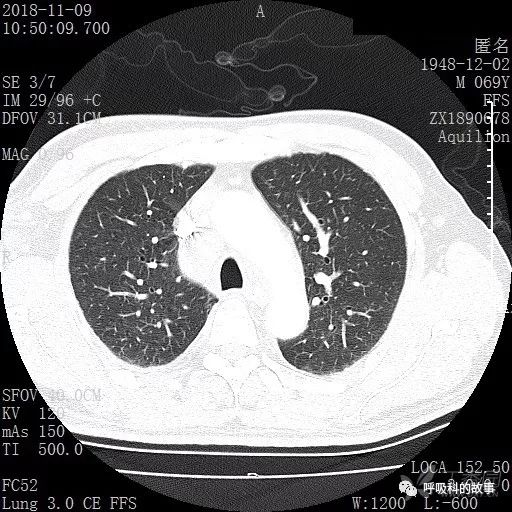

肺窗CT